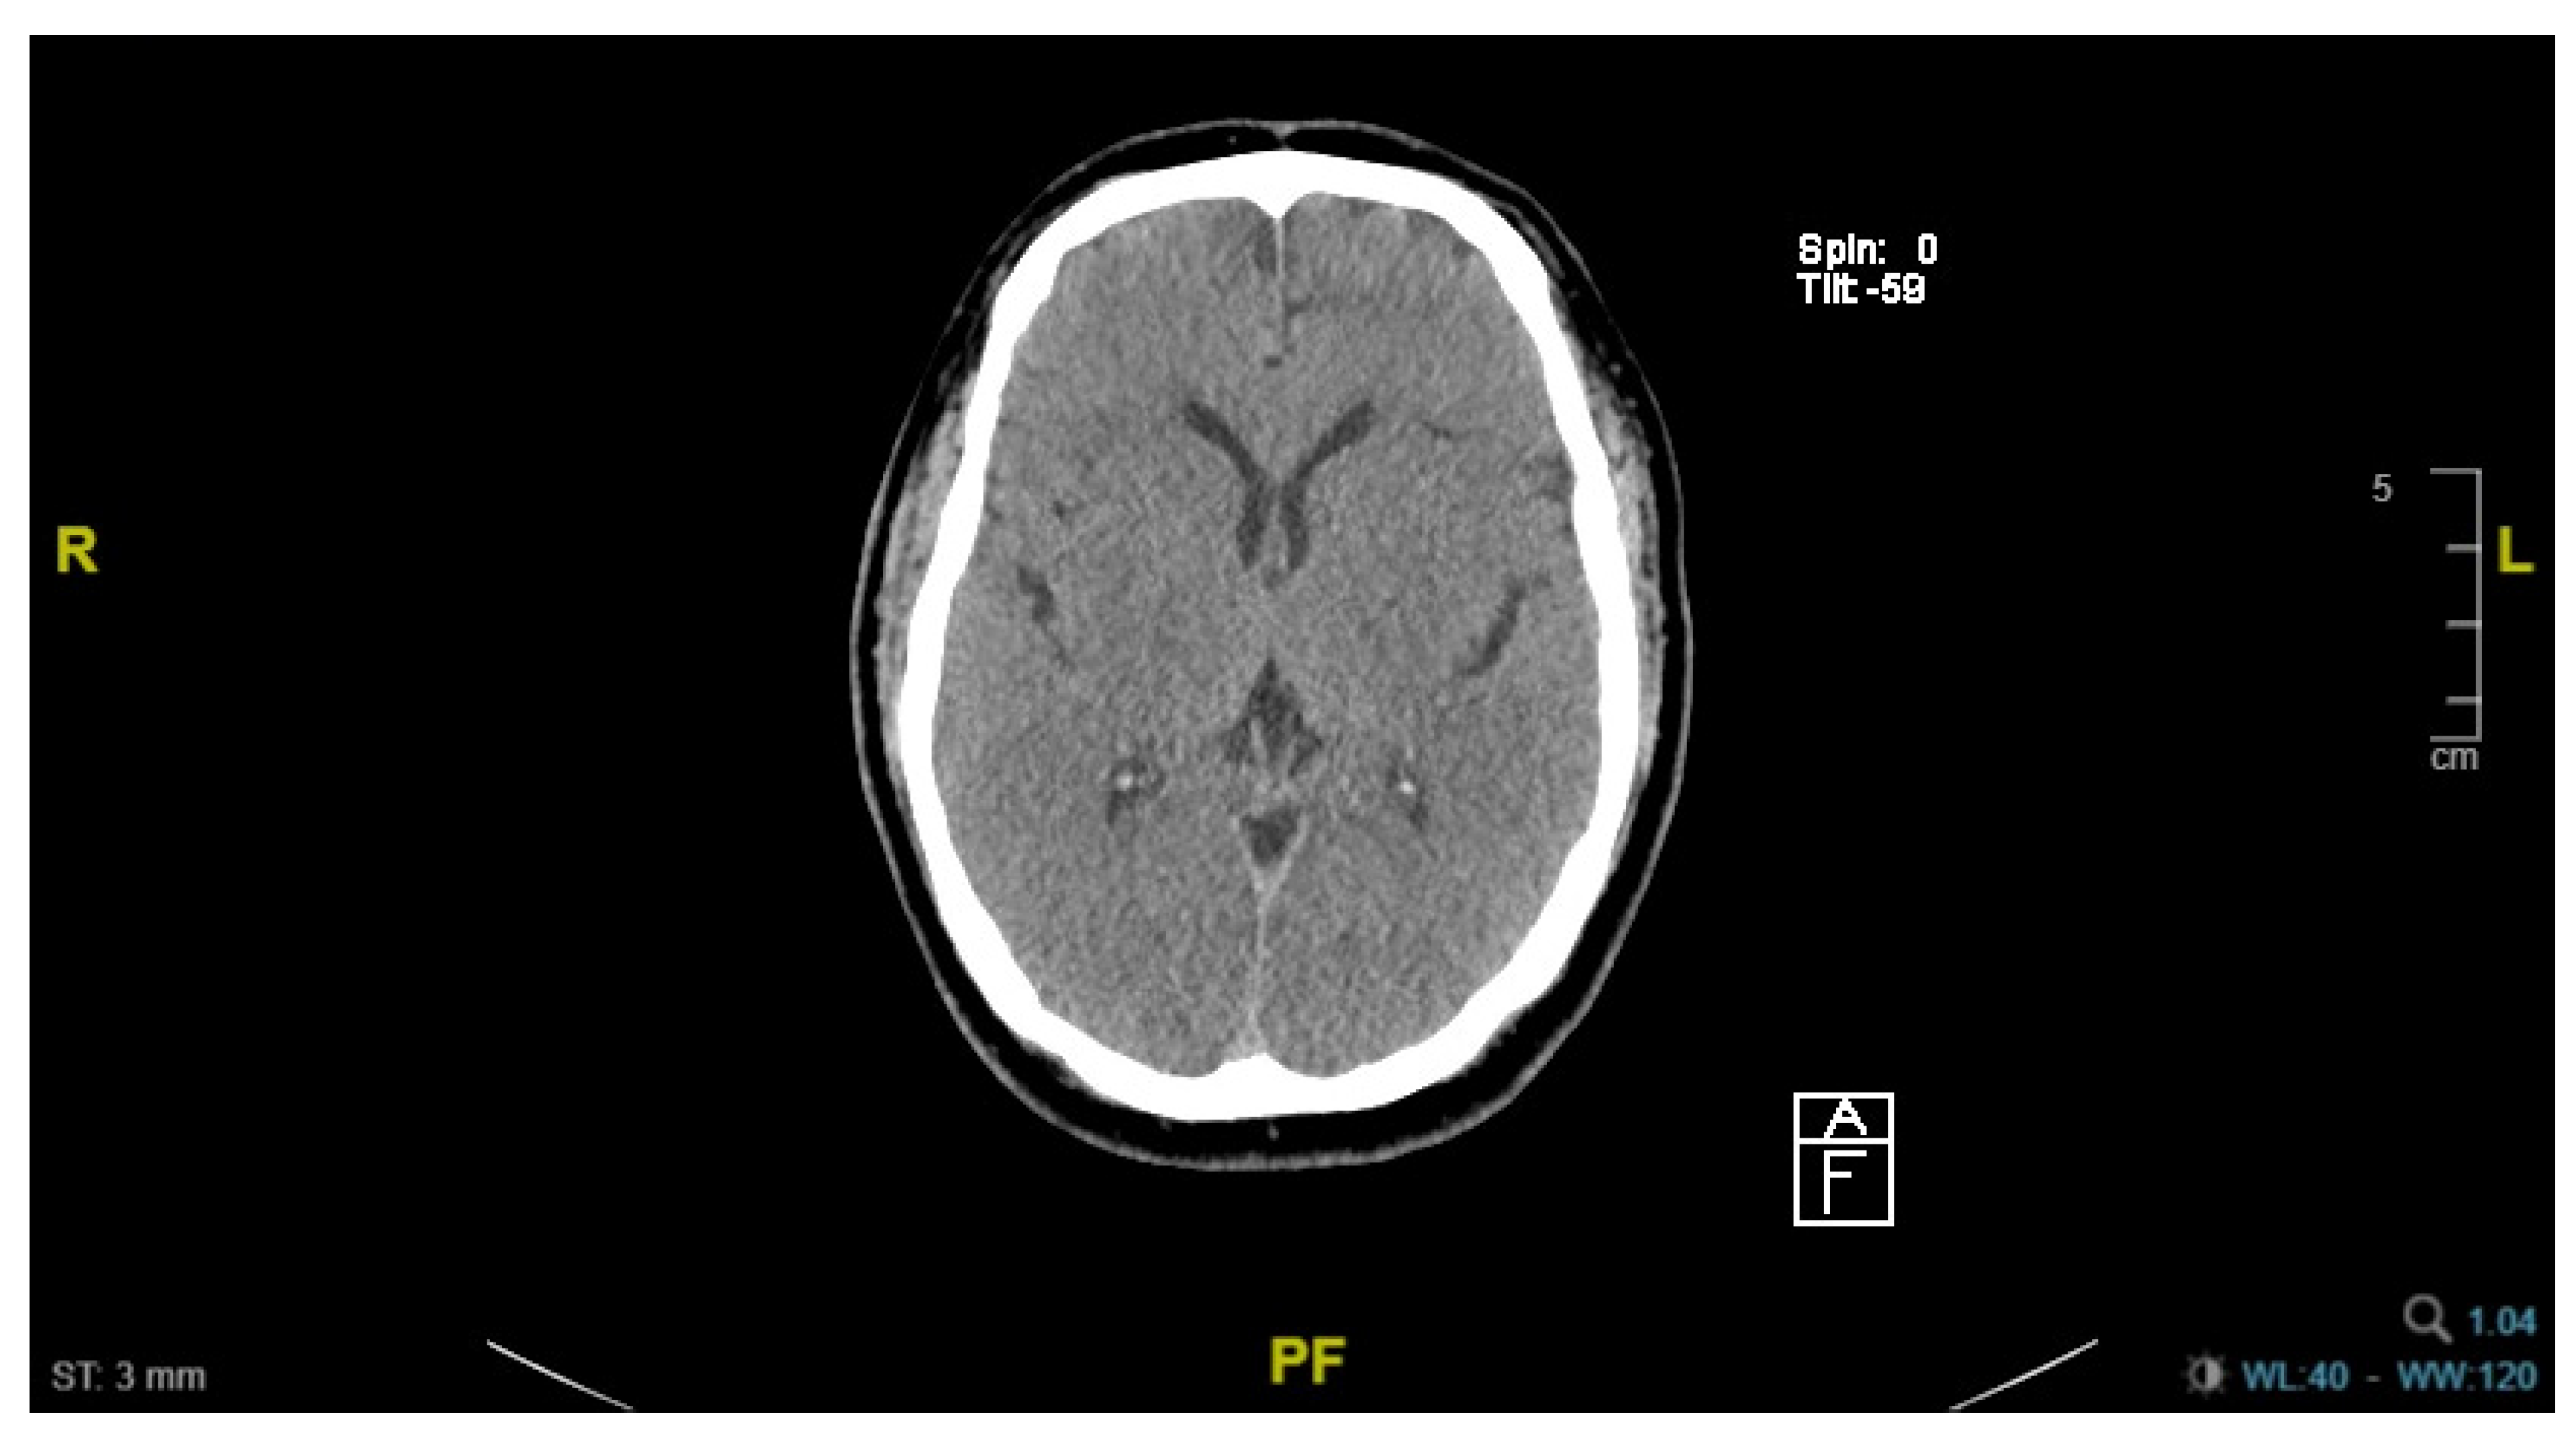

3.3. Patient C